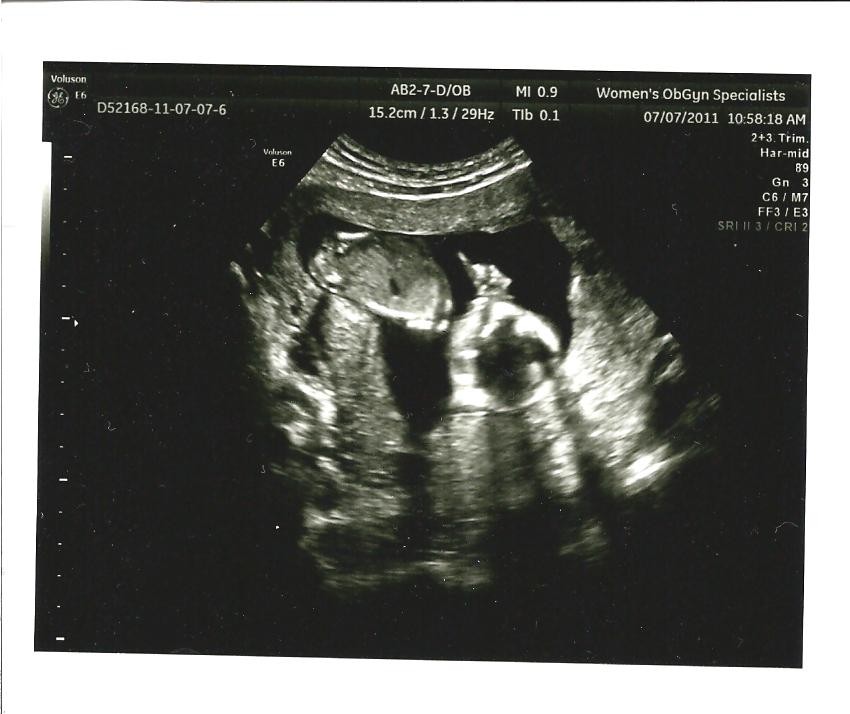

Doctors appointment? No not this week. I went to 2 appointments last week (my OB and a perinatologist for a higher level ultrasound). See the ultrasound pictures below.

Ultrasound pictures:

I had 2 ultrasounds this past week. My OB does an ultrasound every time I see him. I love seeing our baby move. We were able to see the baby sucking its thumb and moving/waving its hand. It was so wonderful to see our little miracle on ultrasound.

![]() |

| Waving hand |

| Sucking thumb |

| Full body profile |

| Close up |